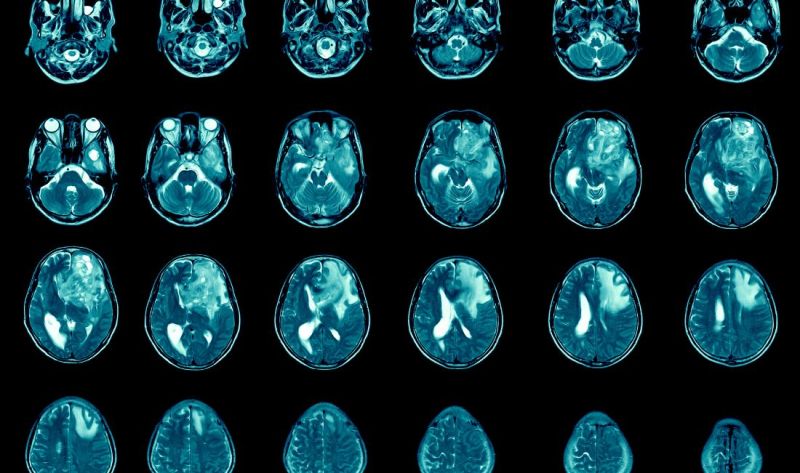

Sofisticirane tehnike snimanja mogu precizno odrediti lokaciju tumora mozga. Dijagnostički alati uključuju kompjutersku tomografiju (CT ili CAT skeniranje) i magnetnu rezonancu (MR) . Intraoperativna MR takođe može biti korisna tokom operacije za vođenje biopsije tkiva i uklanjanje tumora. Spektroskopija magnetne rezonance (MRS) se koristi za ispitivanje hemijskog profila tumora.

• Konvencionalni MR: Magnetna rezonanca (MR) je najvažnija studija snimanja astrocitoma. Obično se slike dobijaju i pre i posle primene kontrasta. Kao pravilo, ako tumor poprimi kontrast (tj. postaje svetao na slikama) je indikacija astrocitoma višeg stepena. Druge sekvence snimanja daju naznake o celularnosti tumora, oticanju mozga i infiltraciji mozga. Tumori niskog stepena obično ne pokazuju mnogo poboljšanja kontrasta, dok GBM pokazuju snažno poboljšanje kontrasta i čestu centralnu nekrozu.